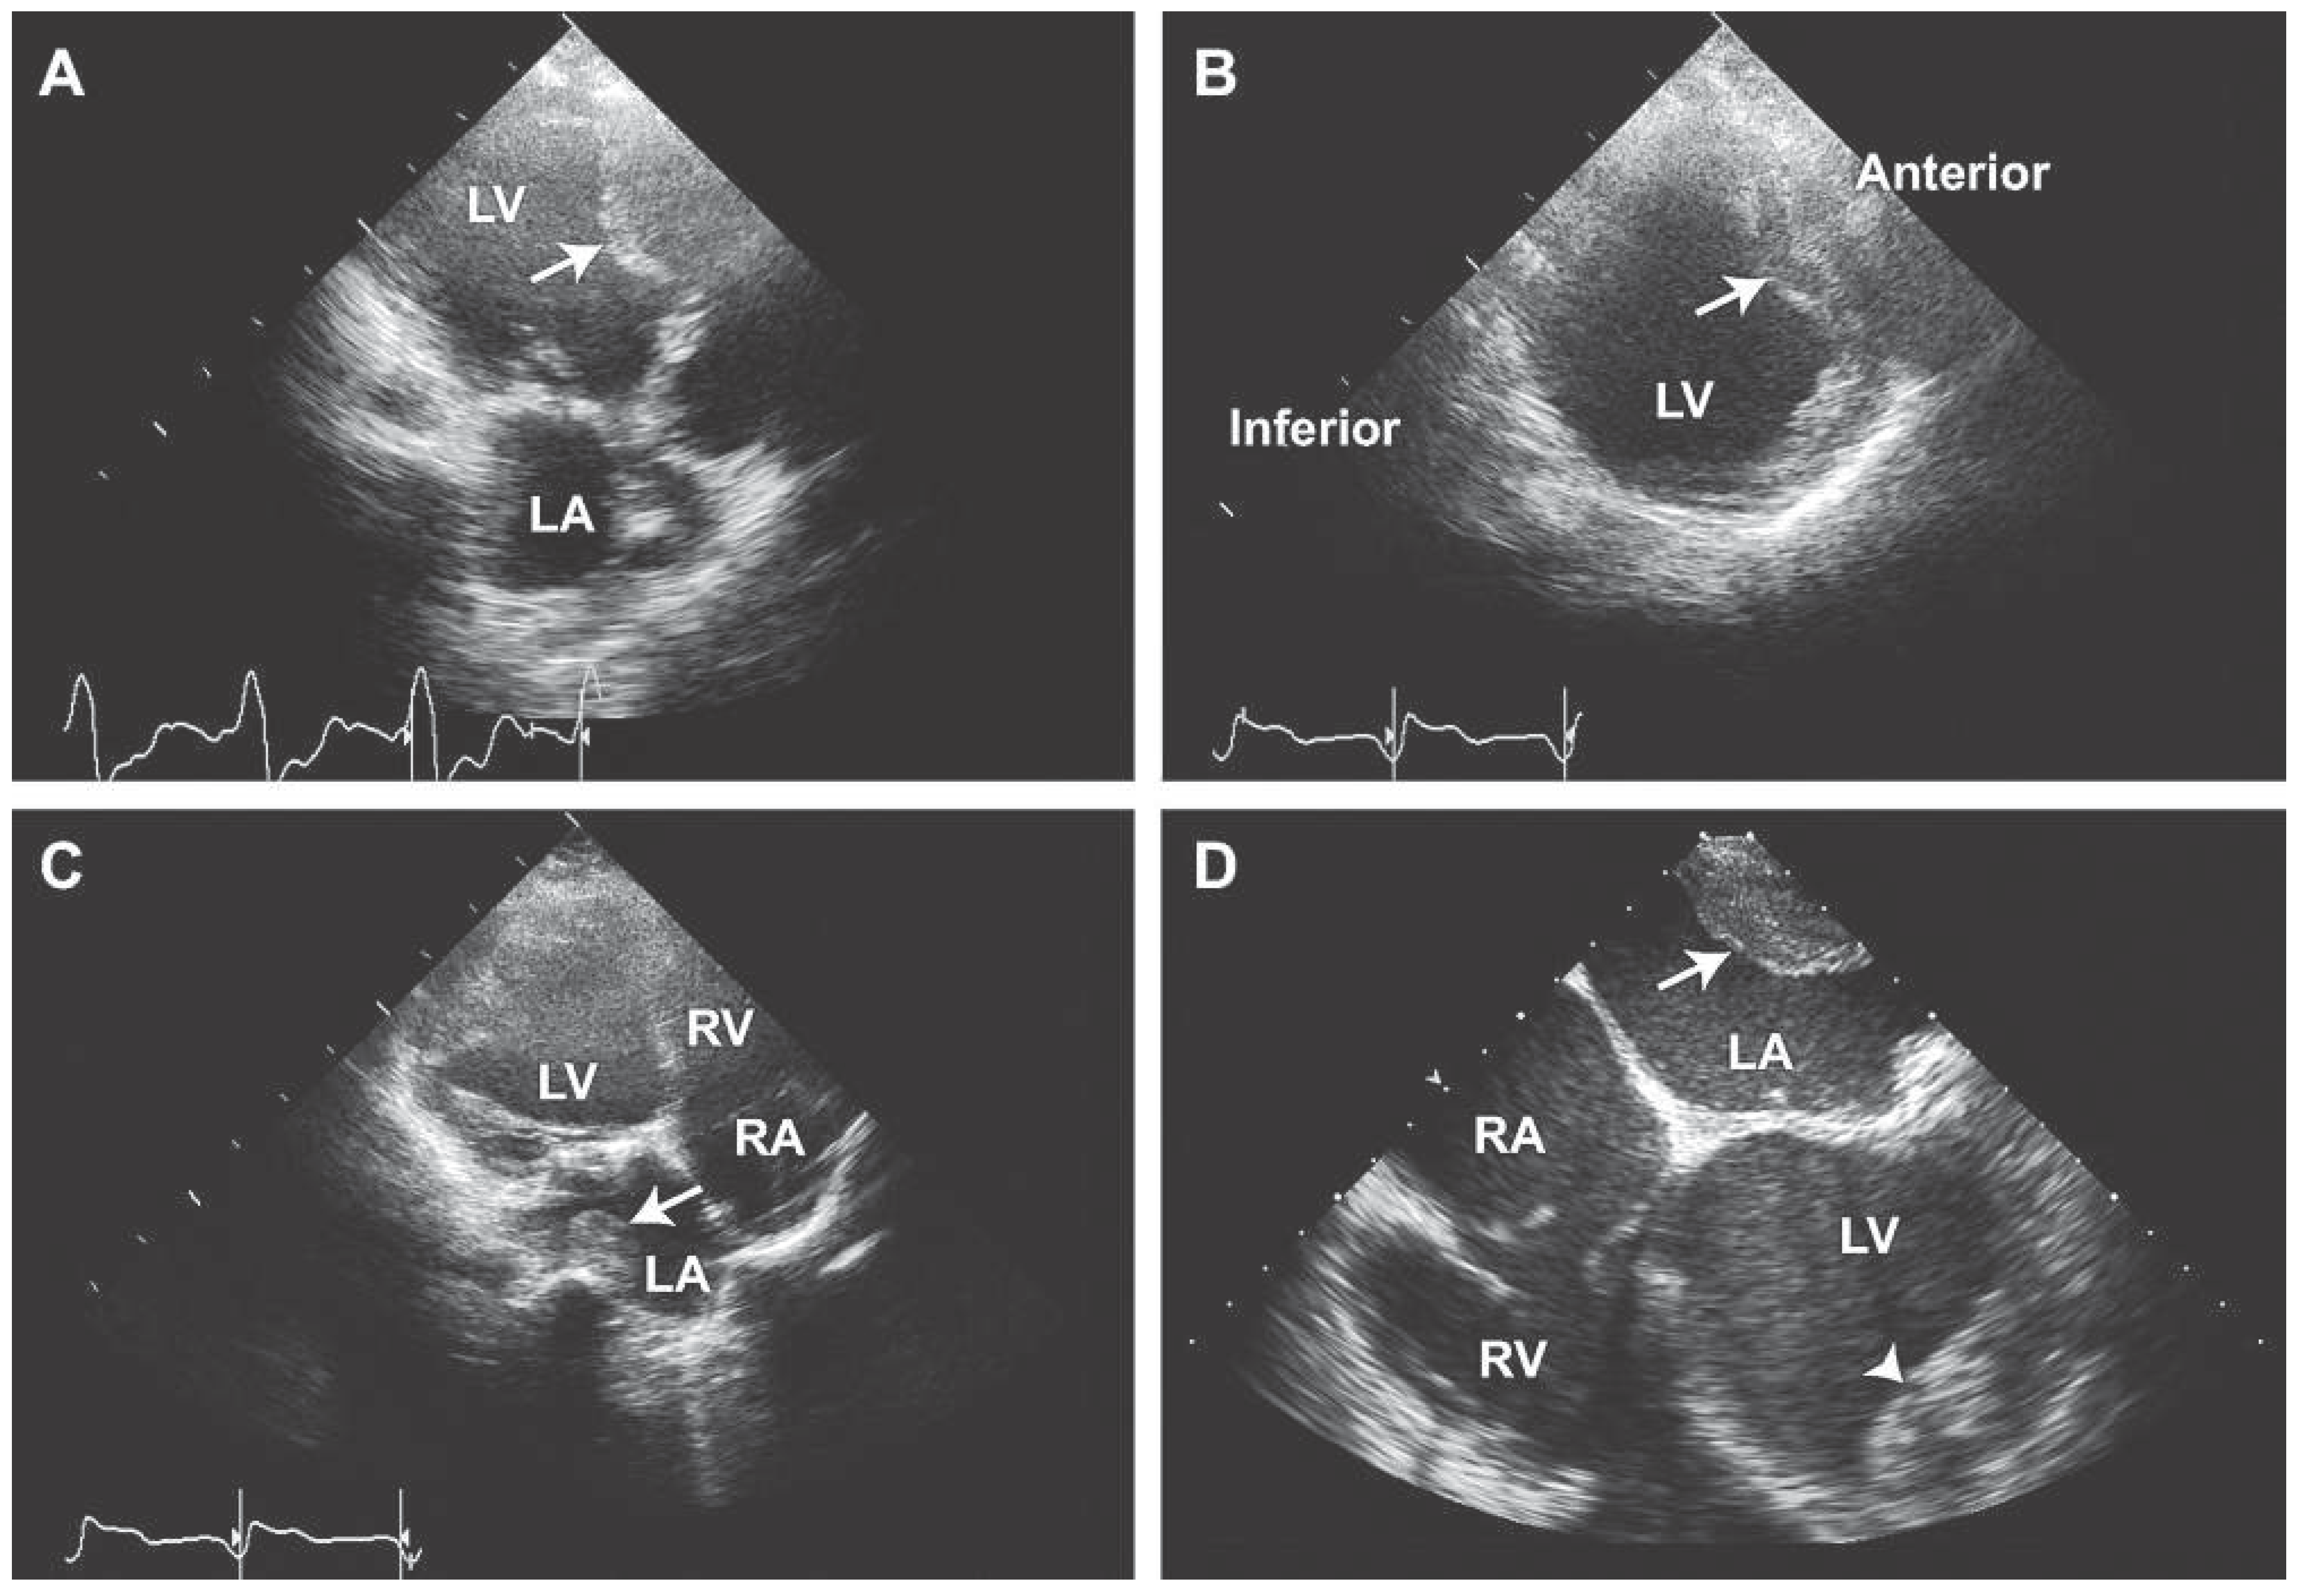

An Unusual Case of Multi-Chamber Thrombi in a Patient with Mitral Valve Repair